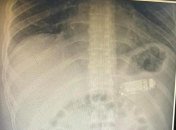

День "пожирателей предметов": в Индии мужчина проглотил телефон, а в Казахстане – 14 крупных гвоздейЖители планеты с трудом переживают трудности последних дней

Медики делали операцию примерно 3 часа.